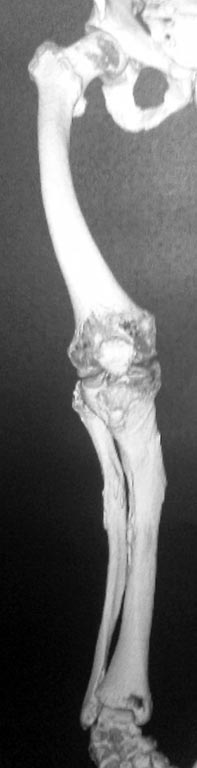

Maxim,

А действительно это Блаунт? Может быть ахондроплазик или дисхондроплазик. 2 недели назад оперировал, поставил обычную компрессионную пластину АО и никакой резекции. И у моего пациента выглядел как псевдартроз. Еще раз порасспрашивайте б-го, может удлиняли бедро? Не забыть бы в понедельник рентгены сфоткать и отправить Вам

А про nail даже и не думайте - канал кривой-косой, очень широкий и короткий